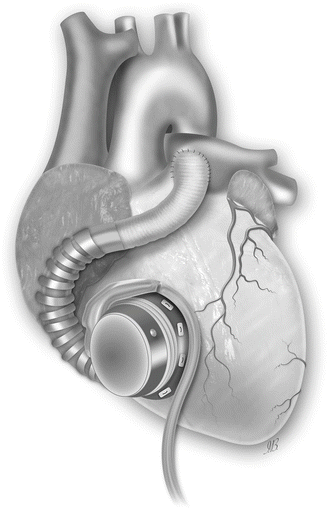

Fig. 31.3

The HVAD pump sewing ring is affixed with interrupted or running sutures to the anterior free wall of the right ventricle (RV) just below the outflow tract. The inflow cannula is then installed through the sewing ring into the RV. Outflow graft is attached to the main pulmonary artery (Picture by Ilaria Bondi’s Peppermint Advertising)